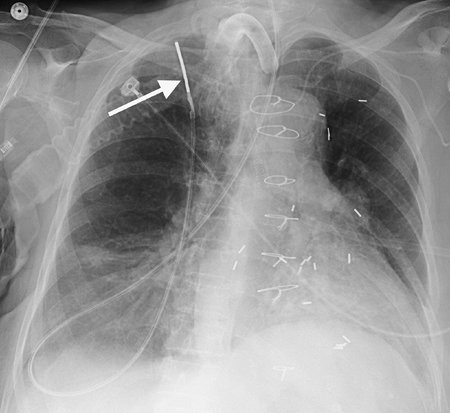

Numerous types of single- and dual-lead pacemakers and combination pacer–defibrillators are available. They are used to treat a variety of dysrhythmias. Accurate interpretation of their appearance on chest radiography requires knowledge of the specific type of pacemaker placed. The three major approaches to insertion of a pacemaker electrode into the heart include epicardial, subxiphoid, and transvenous implantations; transvenous is the most common. With single-lead pacers, the wire is placed into the right ventricle by way of the cephalic, subclavian, or jugular vein. When the lead is wedged into the myocardial trabeculae near the cardiac apex, the lead will be stable and have maximal contact with the endocardial surface. With dual-lead pacers, one lead is generally placed into the right atrium and the other into the right ventricle. It is important to know where the desired placement of leads is for each patient, because placement within the coronary sinus may be accidental or purposeful. After the electrodes are positioned, the generator is placed in a pouch in the subcutaneous tissues of the chest wall or beneath the pectoralis muscle. Biventricular pacemakers are used to treat congestive heart failure. Leads are placed in the right atrium and right ventricle, and a third lead is placed in the coronary sinus for pacing the left ventricle (Fig. 5-18).